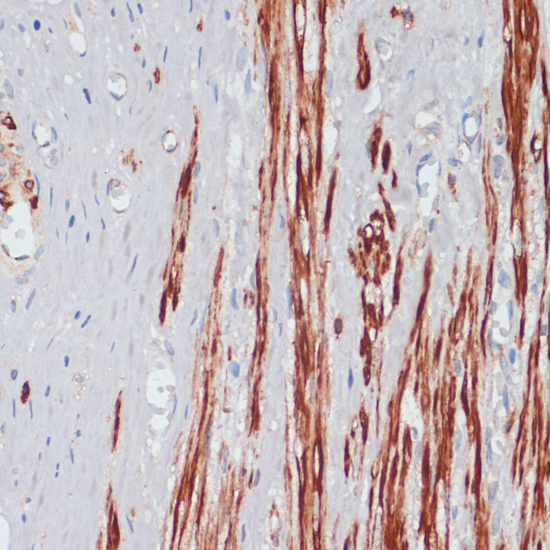

Immunohistochemistry of paraffin-embedded human appendix using DES antibody at dilution of 1:100 (40x lens).

,

Immunohistochemistry of paraffin-embedded rat ovary using DES antibody at dilution of 1:100 (40x lens).

Immunohistochemistry of paraffin-embedded mouse heart using DES antibody at dilution of 1:100 (40x lens).